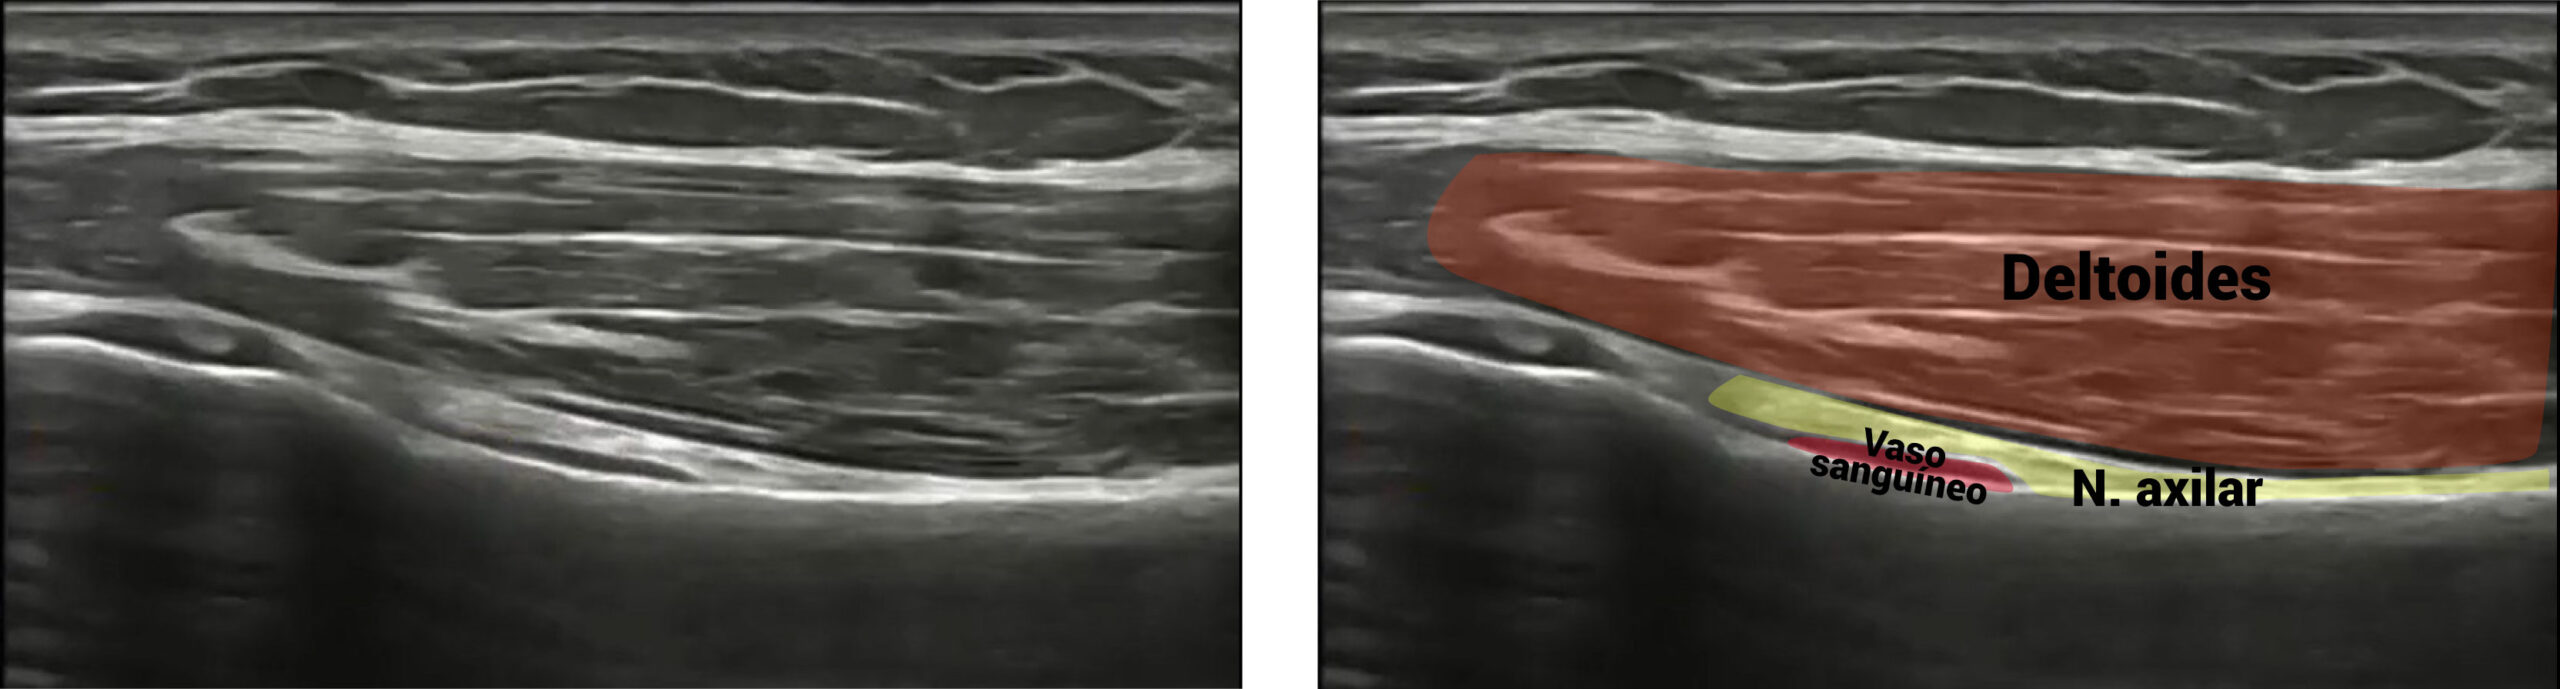

A nivel ecográfico, lo veremos de la siguiente forma:

Abordaje invasivo del nervio axilar o circunflejo

El abordaje que te recomendamos para el nervio axilar o circunflejo, es a través de un corte ecográfico longitudinal. El nervio axilar discurre sobre la cortical del húmero. Deberás tener cuidado con los vasos sanguíneos que lo acompañan, identificándolos como figuras anecoicas en la imagen ecográfica.

Cuando hagamos la estimulación eléctrica, el paciente tendrá una reacción motora del deltoides.